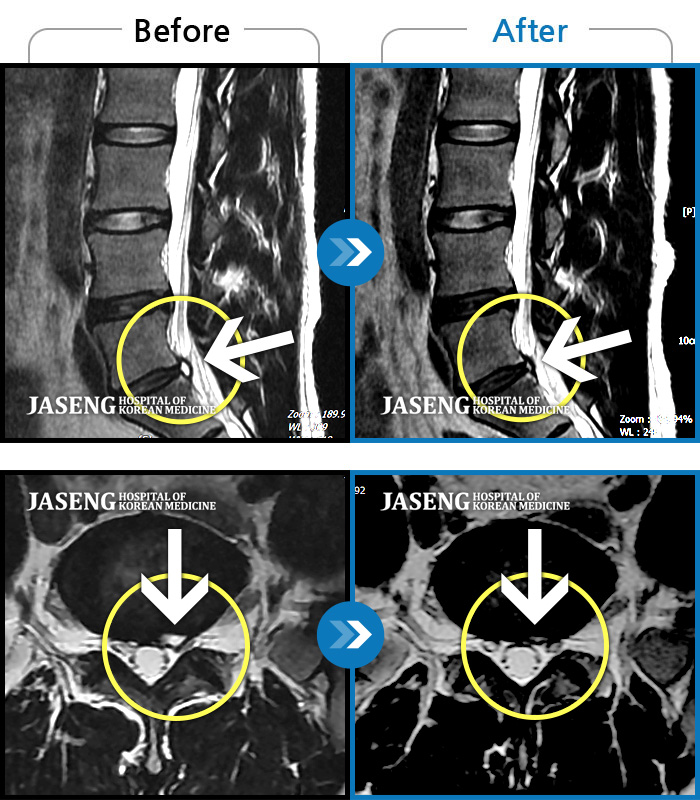

허리디스크

목동 · 고웅 원장

허리통증으로 보행 불가. 우측 다리의 통증과 저림, 화끈거리는 통증과 차가운 느낌 번갈아 나타남

촬영시기

2020.12.18 ~ 2024.11.15

2024.12.24